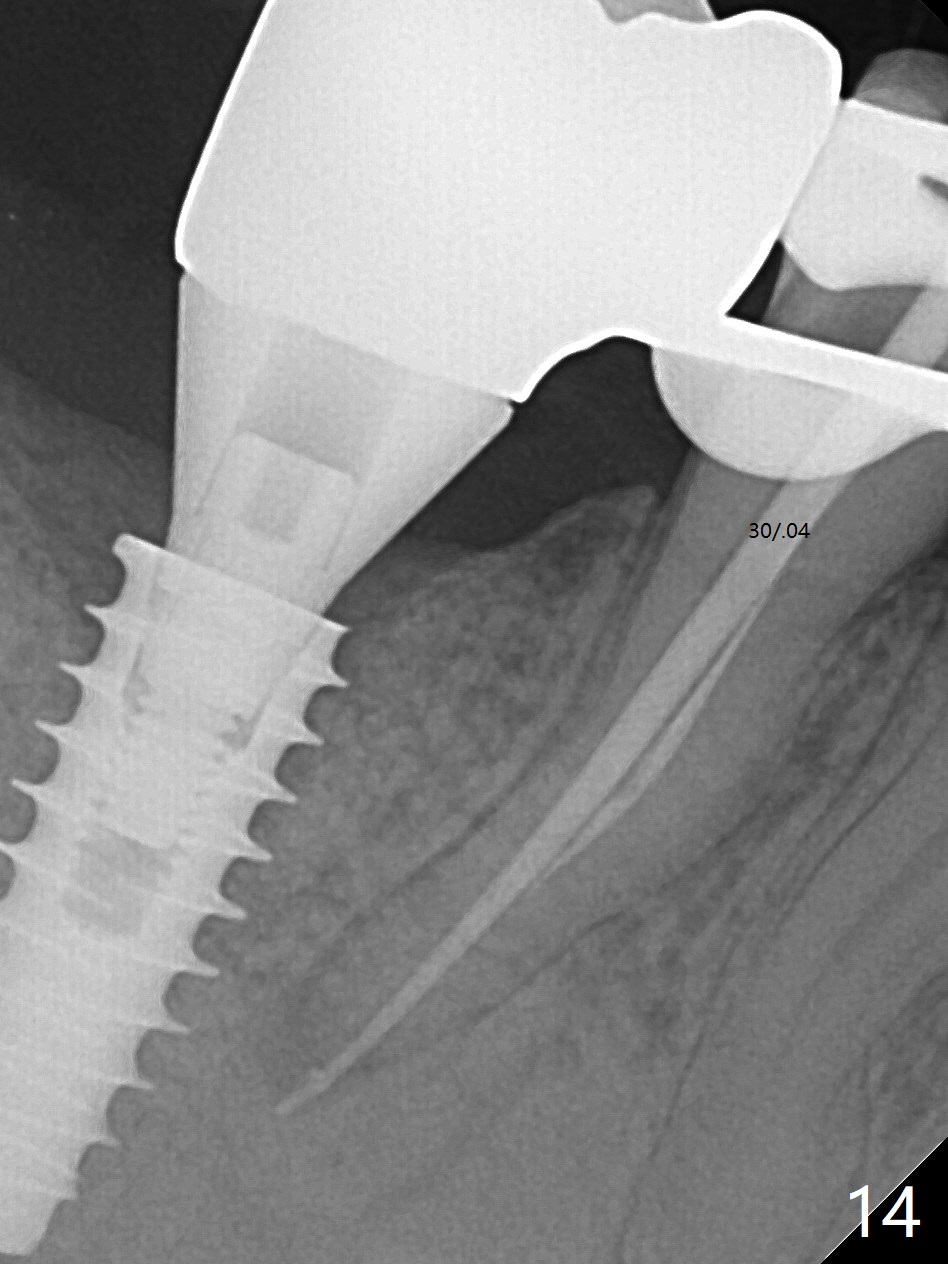

Bone graft seems to sink down and becomes denser 3 months postop (Fig.6 arrow). The bone continues being denser 5 months postop (Fig.7). There is periapical radiolucency of the tooth #29 (^). RCT is done (Fig.8). The pain persists 2 weeks postop (Fig.9,10). There is no missing canal (Fig.9). The apex is close to the implant (Fig.9 *). Apicoectomy will be performed if needed. It appears that the implant is also placed buccal (Fig.10 <) and/or the implant too large for the site. Therefore there should be a 2-3 mm buccal gap before and after implant placement. Separation and reflection of the buccal flap allows better visibility. The pain persists 1 month post RCT and 6 months post implant placement. RCT retreatment is initiated (Fig.11,12) with placement of Calcium Hydroxide paste after redebridement with 30/.04 rotary file at 23.5 mm (.5 mm longer than the earlier RCT, Fig.13). RCT retreatment finishes with apparent transportation and extrusion in 4 weeks (Fig.14,15), followed by apicoetomy (Fig.16,17) (20 days later)). Discomfort remains 2.5 months postop (Fig.18). Keep watching.